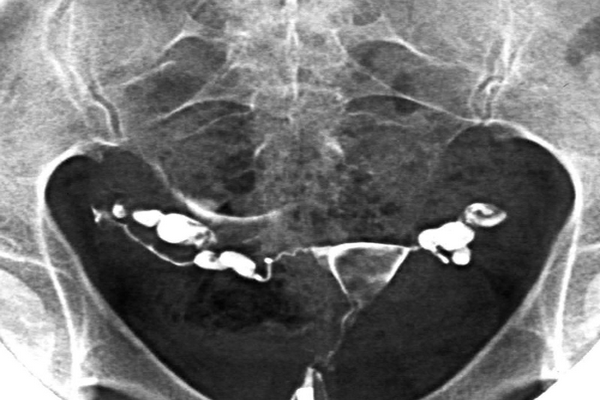

- гистеросальпингография, изучающая состояние и проходимость маточных труб, а также уточняющая возможное развитие новообразование в области матки.

Трансвагинальное или комбинированное гинекологическое УЗИ дополняет и уточняет данные гинекологического осмотра. Эхографически визуализируются расширенные вытянутые фаллопиевы трубы с однородным (при гидросальпинксе) или неоднородным (при пиосальпинксе) содержимым. Рядом с утолщенной трубой определяется интактный яичник. В прямокишечно-маточном углублении может выявляться свободная жидкость. Уточнить проходимость маточных труб и выявить патологию помогает гистеросальпингография и УЗ ГСС.

Врачи чаще всего используют гистеросальпингограмму для диагностики гидросальпинкса. Это рентгенологическое исследование фаллопиевой трубы с использованием тонкого катетера, введенного через шейку матки и матку для введения красителя, который показывает контур фаллопиевой трубы. Серия рентгеновских снимков показывает заполнение фаллопиевых труб, показывая врачу, заблокированы ли фаллопиевы трубы.

- Гистеросальпингограмма (ГСГ): ГСГ — это тип рентгена, который может показать матку и фаллопиевы трубы. Врачи часто используют его для выявления закупорки маточных труб. Процедура предполагает введение специального красителя, видимого на рентгеновском снимке, через влагалище и шейку матки.